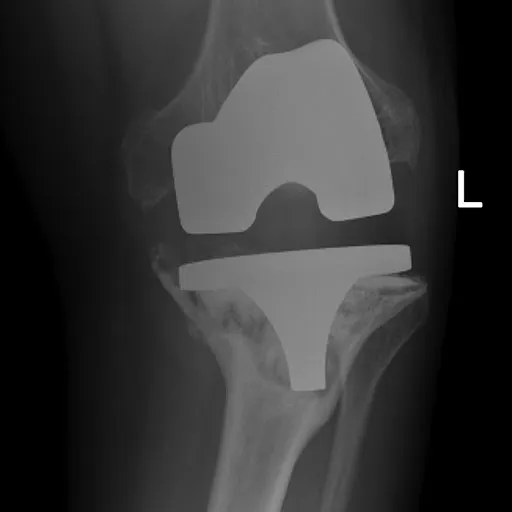

Bone Loss

Repairing or replacing implants impacted by weakened or damaged bone.